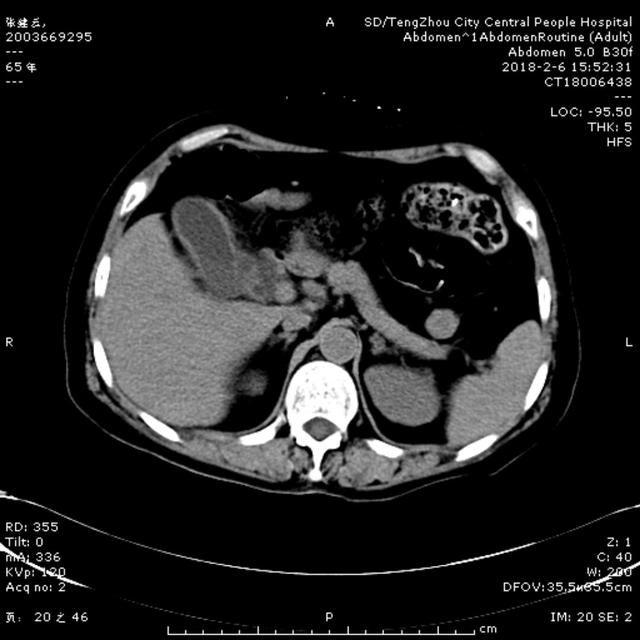

2月6日15:00,一65歲女性患者,因腹痛5天,伴寒戰(zhàn),發(fā)熱,惡心,嘔吐,在當(dāng)?shù)卦\所治療,效果差,以“腹痛待查”收住消化內(nèi)二科。入院查體:體溫37.1℃ 血壓140/90mmHg,急性病容,鞏膜輕度黃染,心肺未及異常,腹部平坦,右上腹壓痛伴反跳痛,肝區(qū)叩擊痛陽性,雙下肢無水腫。入院后給予抗炎、補(bǔ)液處理。急查肝功示谷丙轉(zhuǎn)氨酶561U/L, 谷草轉(zhuǎn)氨酶798U/L, 總膽紅素64.9umol/L ,直接膽紅素58.9umol/L,血常規(guī)示白細(xì)胞5.44X10^9/L, 中性粒細(xì)胞4.69X10^9/L,凝血常規(guī)示正常,行腹部CT可見膽囊壁增厚,膽總管擴(kuò)張,考慮膽系感染、 膽總管結(jié)石可能性大。